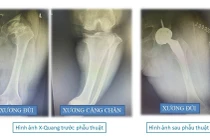

Đây là trường hợp thay khớp háng nhân tạo cực kỳ đặc biệt. Bệnh nhân bị ảnh hưởng chất độc màu da cam, rối loạn phát triển hệ vận động dẫn đến toàn bộ vùng ổ cối xương chậu không phát triển....